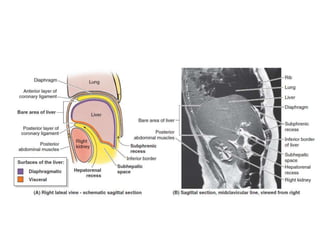

The document lists the key anatomical structures and vasculature of the inguinal region and abdominal cavity. It outlines the ligaments and fascial layers that make up the inguinal canal. It then describes the branches of the celiac trunk, superior mesenteric artery, and inferior mesenteric artery that supply the gastrointestinal tract and associated organs. Finally, it briefly mentions the major abdominal veins, including the hepatic, portal, mesenteric and inferior veins.